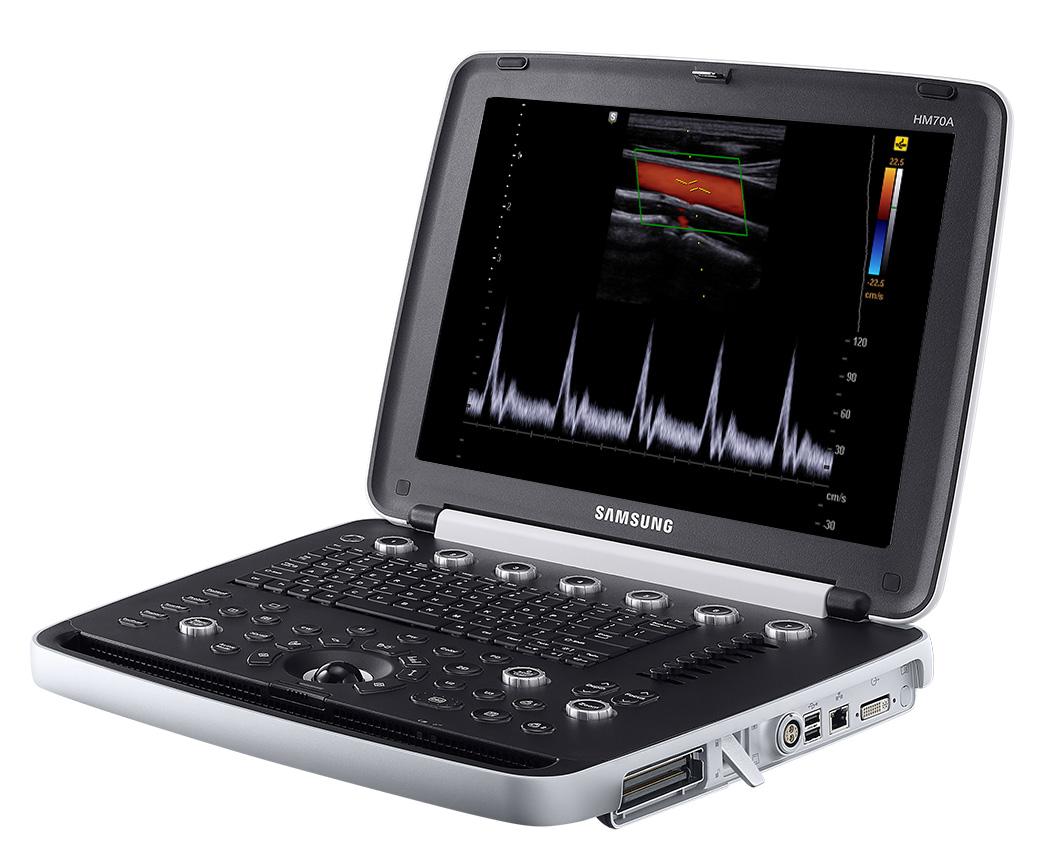

HM70 EVO SAMSUNG

Samsung Ultrasound HM70A

Samsung Ultrasound HM70A